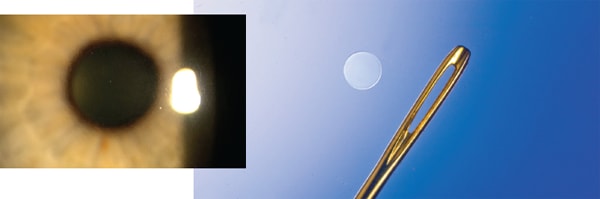

A rendering of the Kamra corneal inlay as it looks in the eye.

A slit-lamp image of the Flexivue corneal inlay.

Smaller than a needle thread hole, the Raindrop inlay as it appears in the eye.